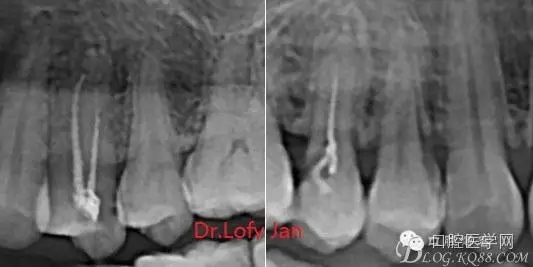

前言:自己做的一些曲面斷層片在未試尖根管治療中的病例整理,發(fā)現(xiàn)問題很多包括自身的,技術(shù)的,還有設(shè)備的問題,予以總結(jié)整理并期待進(jìn)一步提高。

病例分析:曲面斷層片在x線輔助診斷與檢查中目前大多數(shù)文獻(xiàn)和著作都建議只能作為初診拍片檢查手段,不能作為終末疾病的確診與手術(shù)療效的評價(jià)指標(biāo),臨床大部分中小型門診都因?yàn)樵O(shè)備不齊全導(dǎo)致信息偏差很大。